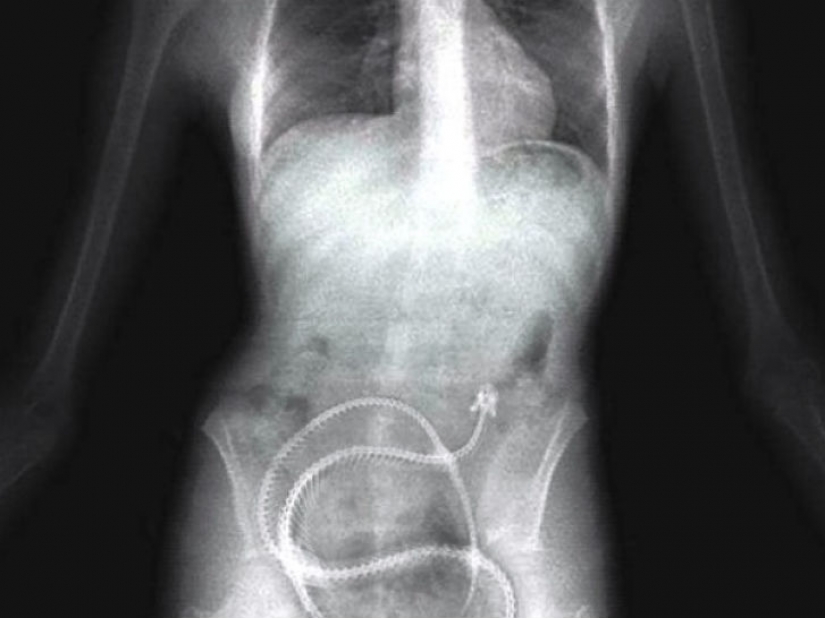

And it looks like the man who swallowed a considerable quantity of drugs to carry their contraband across the border.

Some inmates are willing to swallow anything just to get out of prison, for example, in the hospital — even the springs from the mattress.